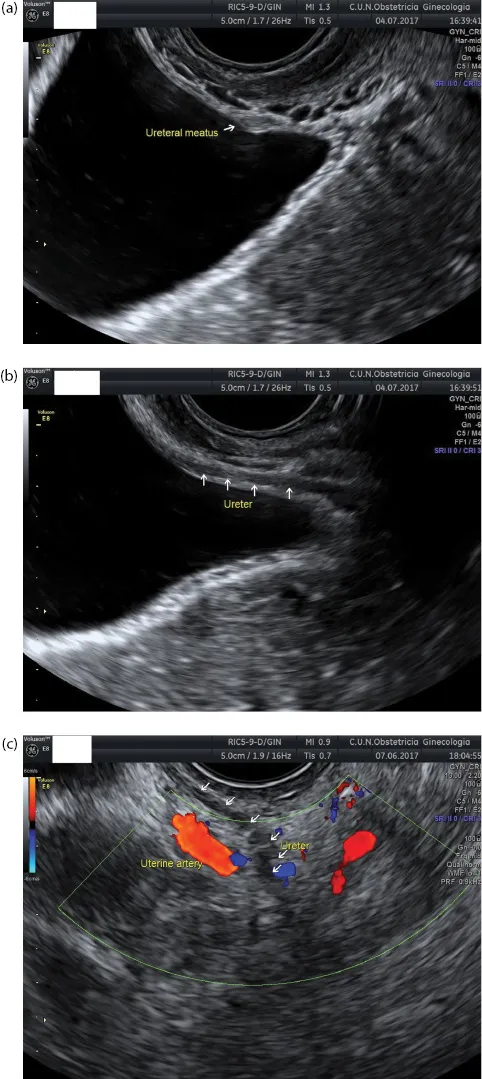

The ureters can be seen passing through the bladder wall, and the ureteral meatus can be identified in both sides (Figure 1.5a). They are commonly identified as a hypoechoic creeping structure within the bladder wall (Figure 1.5b). More laterally, they can be observed crossing under the uterine artery (Figure 1.5c).

Figure 1.5 (a) Transvaginal ultrasound showing the bladder. The ureteral meatus can be observed in the longitudinal plane moving the endovaginal transducer laterally. (b) The transmural portion of the u...